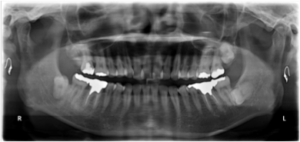

下の写真は50歳代後半の方の治療前の状態です(図1、2)。

きれいに手入れされていますが年齢相応の歯と歯茎の劣化が認められます。

図1(治療前)

図2(治療前)

下はレントゲン写真です。歯を支えている骨には異常がありません。

図3(治療前レントゲン)